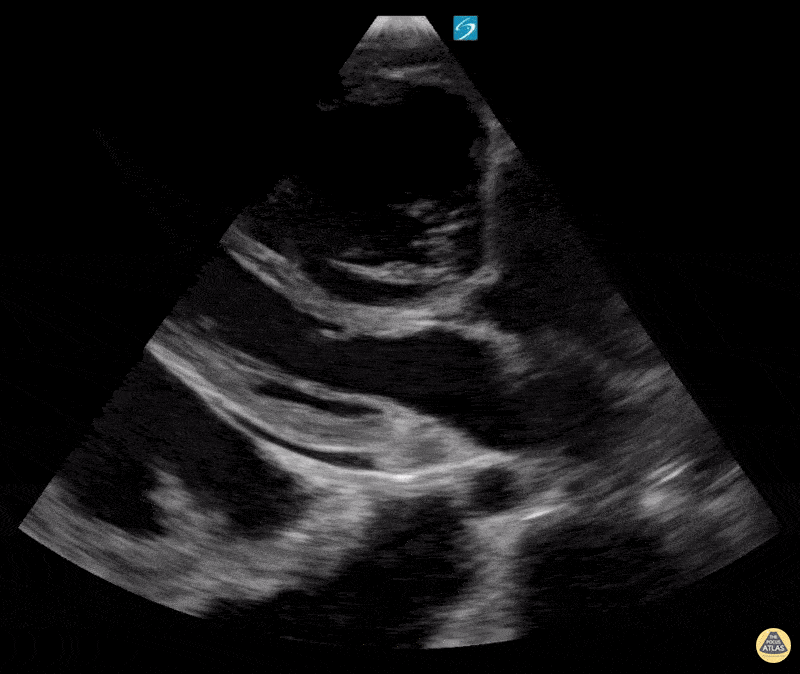

28 yo M PMH Pulmonary Hypertension (PH) group 1 and 4, RV failure due to PH, invasive pulmonary aspergillosis in MICU for mixed shock (Cardiogenic vs Sepsis). Lethargic with high needs for Heated High Flow Nasal Canula. RV failure is noted with significant RV and RA dilation with bowing of interventricular septum into LVOT as well as McConnell's sign. Patient also has a pericardial effusion, bilateral pleural effusions and ascites. Erick Otiniano, MD MPH | DHREM PGY1